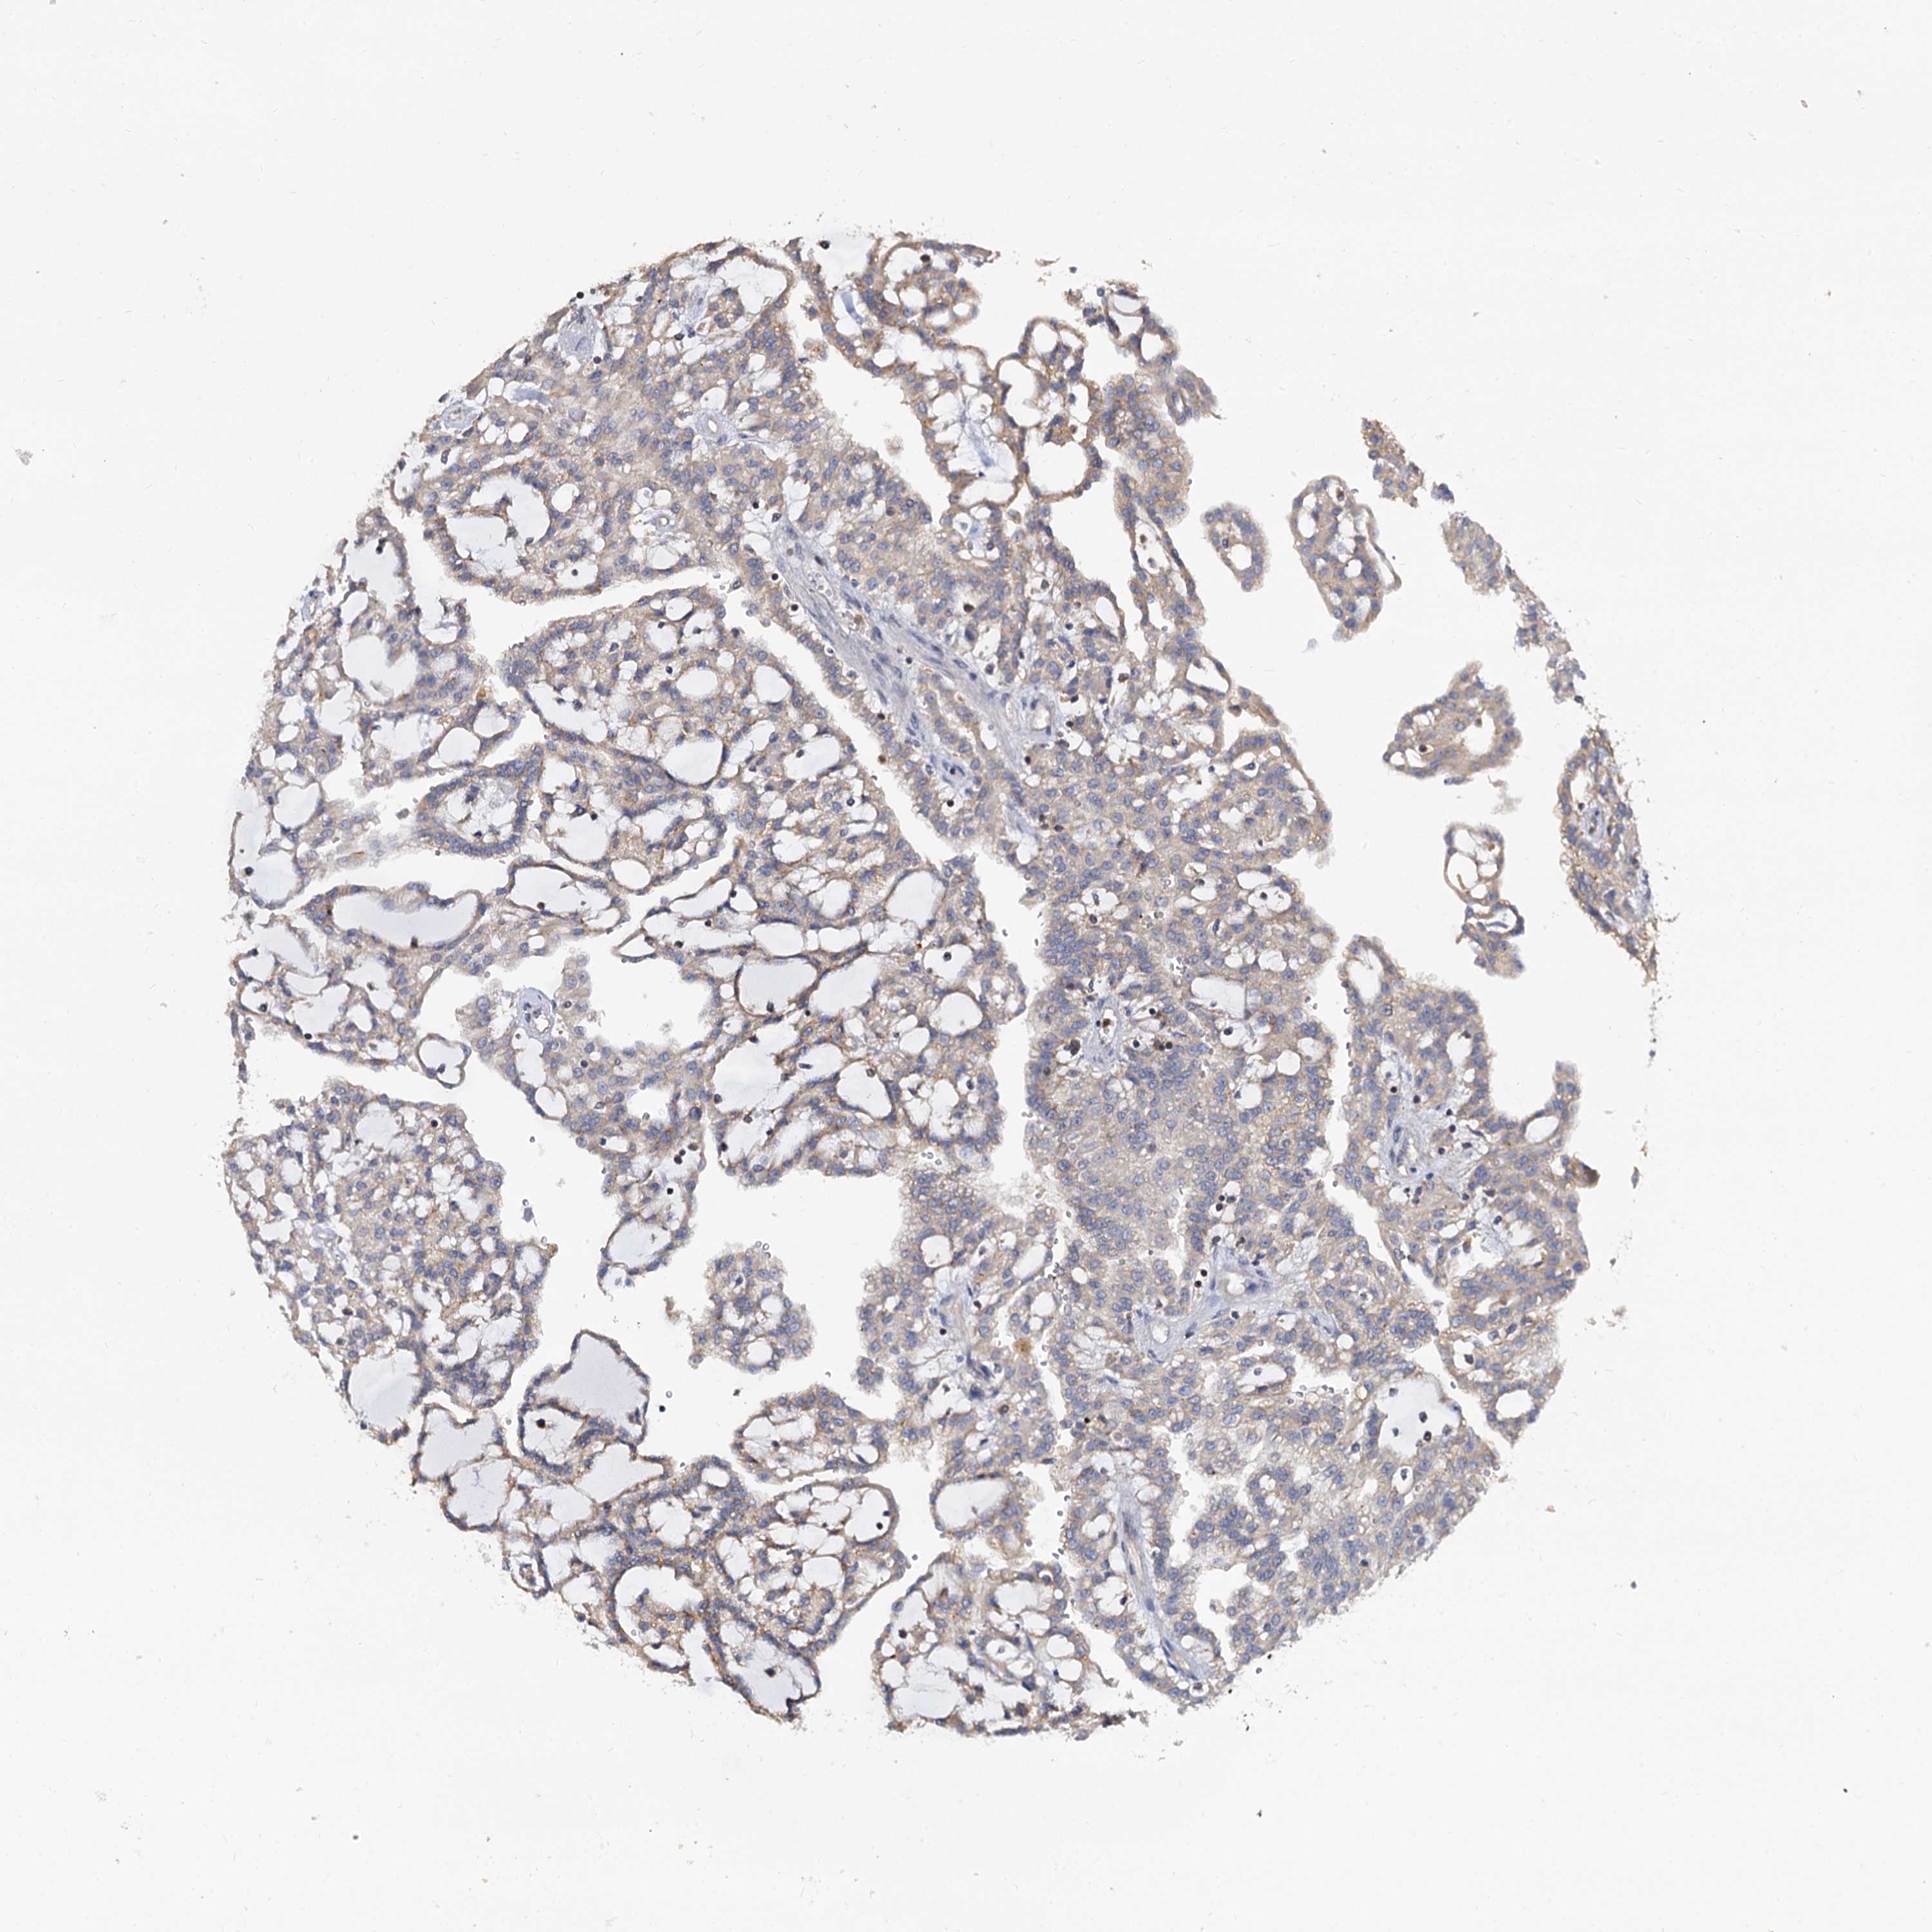

KIDNEY RENAL CLEAR CELL CARCINOMA (VALIDATION) - Interactive survival scatter ploti

The Survival Scatter plot shows the clinical status (i.e. dead or alive) for all individuals in the patient cohort, based on the same data that underlies the corresponding Kaplan-Meier plots. Patients that are alive at last time for follow-up are shown in blue and patients who have died during the study are shown in red.

The x-axis shows the expression levels (FPKM) of the investigated gene in the tumor tissue at the time of diagnosis. The y-axis shows the follow-up time after diagnosis (years). Both axes are complimented with kernel density curves demonstrating the data density over the axes. The top density plot shows the expression levels (FPKM) distribution among dead (red) and alive patients (blue). The right density plot shows the data density of the survived years of dead patients with high and low expression levels respectively, stratified using the cutoff indicated by the vertical dashed line through the Survival Scatter plot. This cutoff is automatically defined based on the FPKM cutoff that minimizes the p-score. The cutoff can be changed by dragging the vertical line or by entering a cutoff value in the square labeled "Current cut-off".

Under the Survival Scatter plot the p-score landscape (black curve; left axis) is shown together with dead median separation (red curve; right axis). Dead median separation is the difference in median mRNA expression between patients who have died with high and low expression, respectively. It is calculated as follows: median FPKM expression of dead patients with high expression - median FPKM expression of dead patients with low expression. This is intended to aid the user in visually exploring custom cutoffs and the associated p-scores and dead median separation.

Individual patient data is displayed and can be filtered by clicking on one or more of the category buttons on the top of the page. Categories describing expression level and patient information include: high, low, alive, dead, female, male and tumor stages. The scale of the x-axis can be toggled between linear and log-scale by clicking on the "x log" button. Mouse-over function shows TCGA ID, patient information and mRNA expression (FPKM) for each patient.

& Survival analysisi

Kaplan-Meier plots summarize results from analysis of correlation between mRNA expression level and patient survival. Patients were divided based on level of expression into one of the two groups "low" (under cut off) or "high" (over cut off). X-axis shows time for survival (years) and y-axis shows the probability of survival, where 1.0 corresponds to 100 percent.

ANKRD13A is not prognostic in Kidney Renal Clear Cell Carcinoma (validation)

Best expression cut offi

Based on the FPKM value of each gene, patients were classified into two groups and association between prognosis (survival) and gene expression (FPKM) was examined. The best expression cut-off refers the FPKM value that yields maximal difference with regard to survival between the two groups at the lowest log-rank P-value. Best expression cut-off was selected based on survival analysis .

When clicking on this number, the vertical dashed line indicating cut-off, the interactive survival plot, and the Kaplan-Meier curve will be adjusted to show results based on the best expression cut-off.

: 34.33

P scorei

Log-rank P value for Kaplan-Meier plot showing results from analysis of correlation between mRNA expression level and patient survival.

N/A

TCGA RNA samplesi

RNA-seq data is reported as average FPKM (number Fragments Per Kilobase of exon per Million reads), generated by the The Cancer Genome Atlas (TCGA) .

Normal distribution across the dataset is visualized with box plots, shown as median and 25th and 75th percentiles. Points are displayed as outliers if they are above or below 1.5 times the interquartile range. FPKM values of the individual samples are presented next to the box plot.

Average pTPM 52.9

Number of samples 100